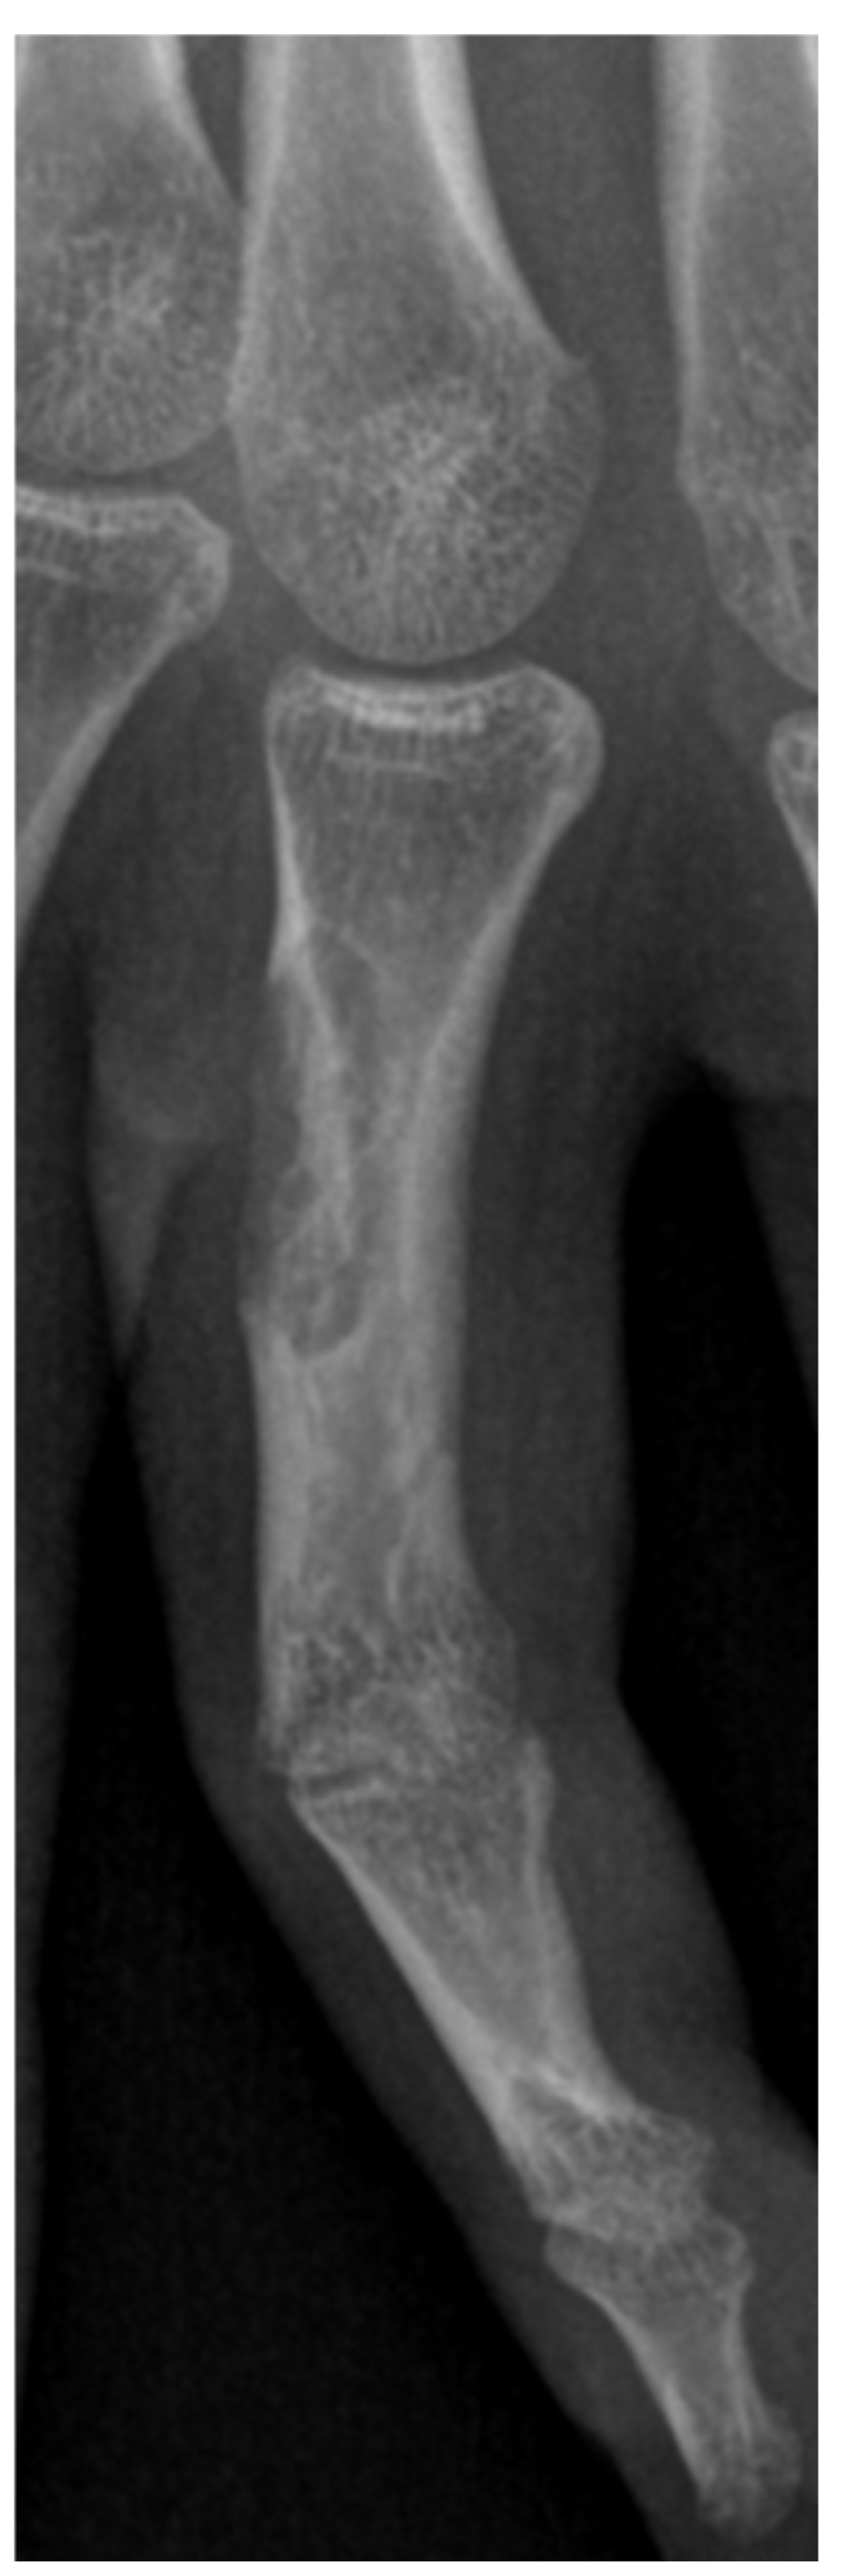

| XRAY | 6 |

| Myoepithelioma | Slow growing | S100 protein, EMA, CK7, AE1/AE3, calponin | X-ray: may show bone erosion MRI: low contrast T1, high contrast T2. May show tendon involvement |